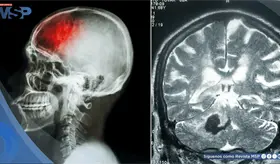

Desde el deterioro vascular asociado a la hipertensión hasta el control quirúrgico de hematomas cerebelosos, el enfoque del ACV depende del tipo de evento y de su localización.